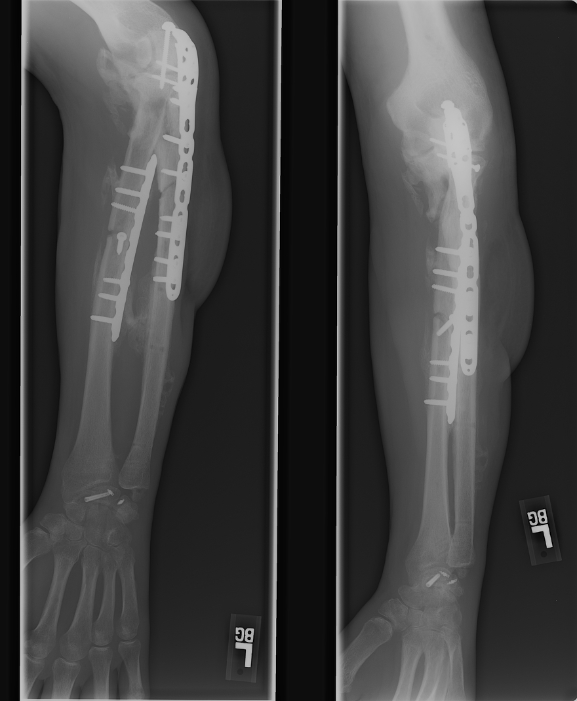

March 13, 2008 This shows the two plates inserted to hold the bone pieces in place. |

Marh 13, 2008 Here you can see the screws near his elbow. |